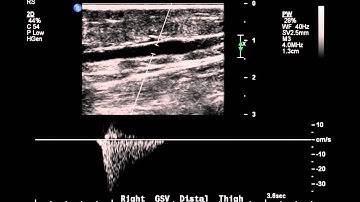

Case study - Reflux in GSV with varicosity